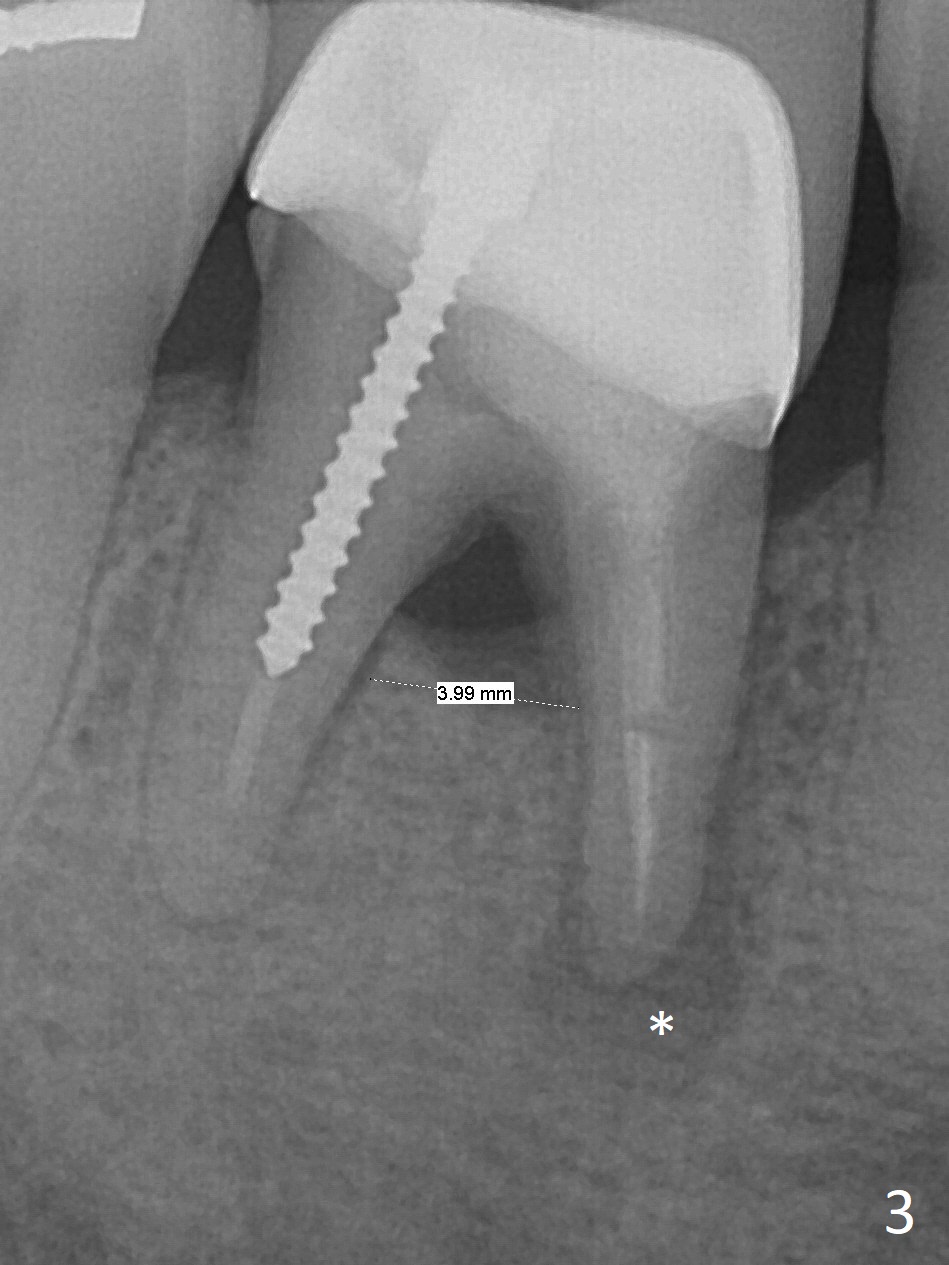

There appears no bone resorption at the septum of the tooth #30 of a 61-year-old man with 22 mm of bone (Fig.1; 10 years ago). The septum starts to have bone loss without symptom 3 years earlier (Fig.2 ^). Now the tooth is symptomatic with bone lesion also involving the mesial apex (Fig.3 *). Osteotomy will be initiated in the flattened septum with 4 mm mesiodistal width. Prior to placing a 13 mm IS implant, the depth of the last 2nd drill will be 15 mm. Prepare Magic Expanders. Place Magic Split blade buccolingually to expand the septum mesiodistally.